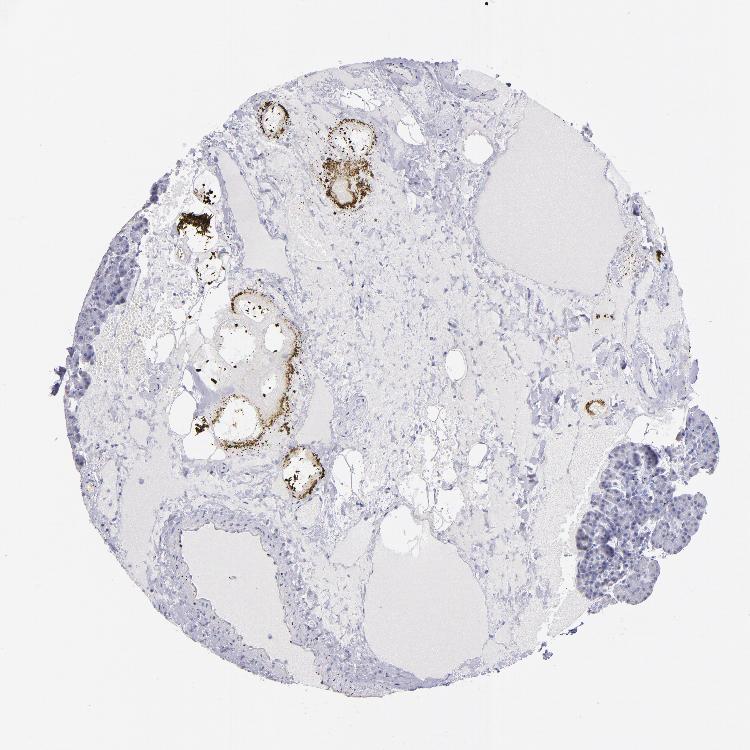

Antibody staining in the annotated cell types in the current human tissue is reported as not detected, low, medium, or high. This score is based on the staining intensity and fraction of stained cells.

Information about each individual sample is listed below, including gender, age, a tissue section image and estimated fractions of cell types. pTPM (transcripts per million) values give a quantification of the gene abundance which is comparable between different genes and samples.